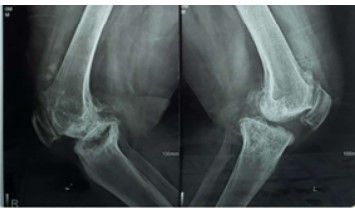

Purpose: Tibial bone defects in total knee arthroplasty (TKA) pose a significant challenge for surgeons, potentially causing improper component balancing. We studied the outcomes of autogenous structural bone grafting

with screws to address medial proximal tibial defects in primary TKA with varus deformity.

Methods: A prospective study was conducted at Elite Hospital’s Orthopedic Department in Sana’a City between

2020 and 2024. Patients with uncontained medial proximal tibial defects 10–25 mm in depth who underwent

primary TKA for varus deformity were managed using autogenous structural bone grafts fixed with screws and

followed up for at least 40 months. Patients were followed up clinically using the Knee Society Score (KSS).

Radiological follow-up was performed to assess bone graft union and implant stability.